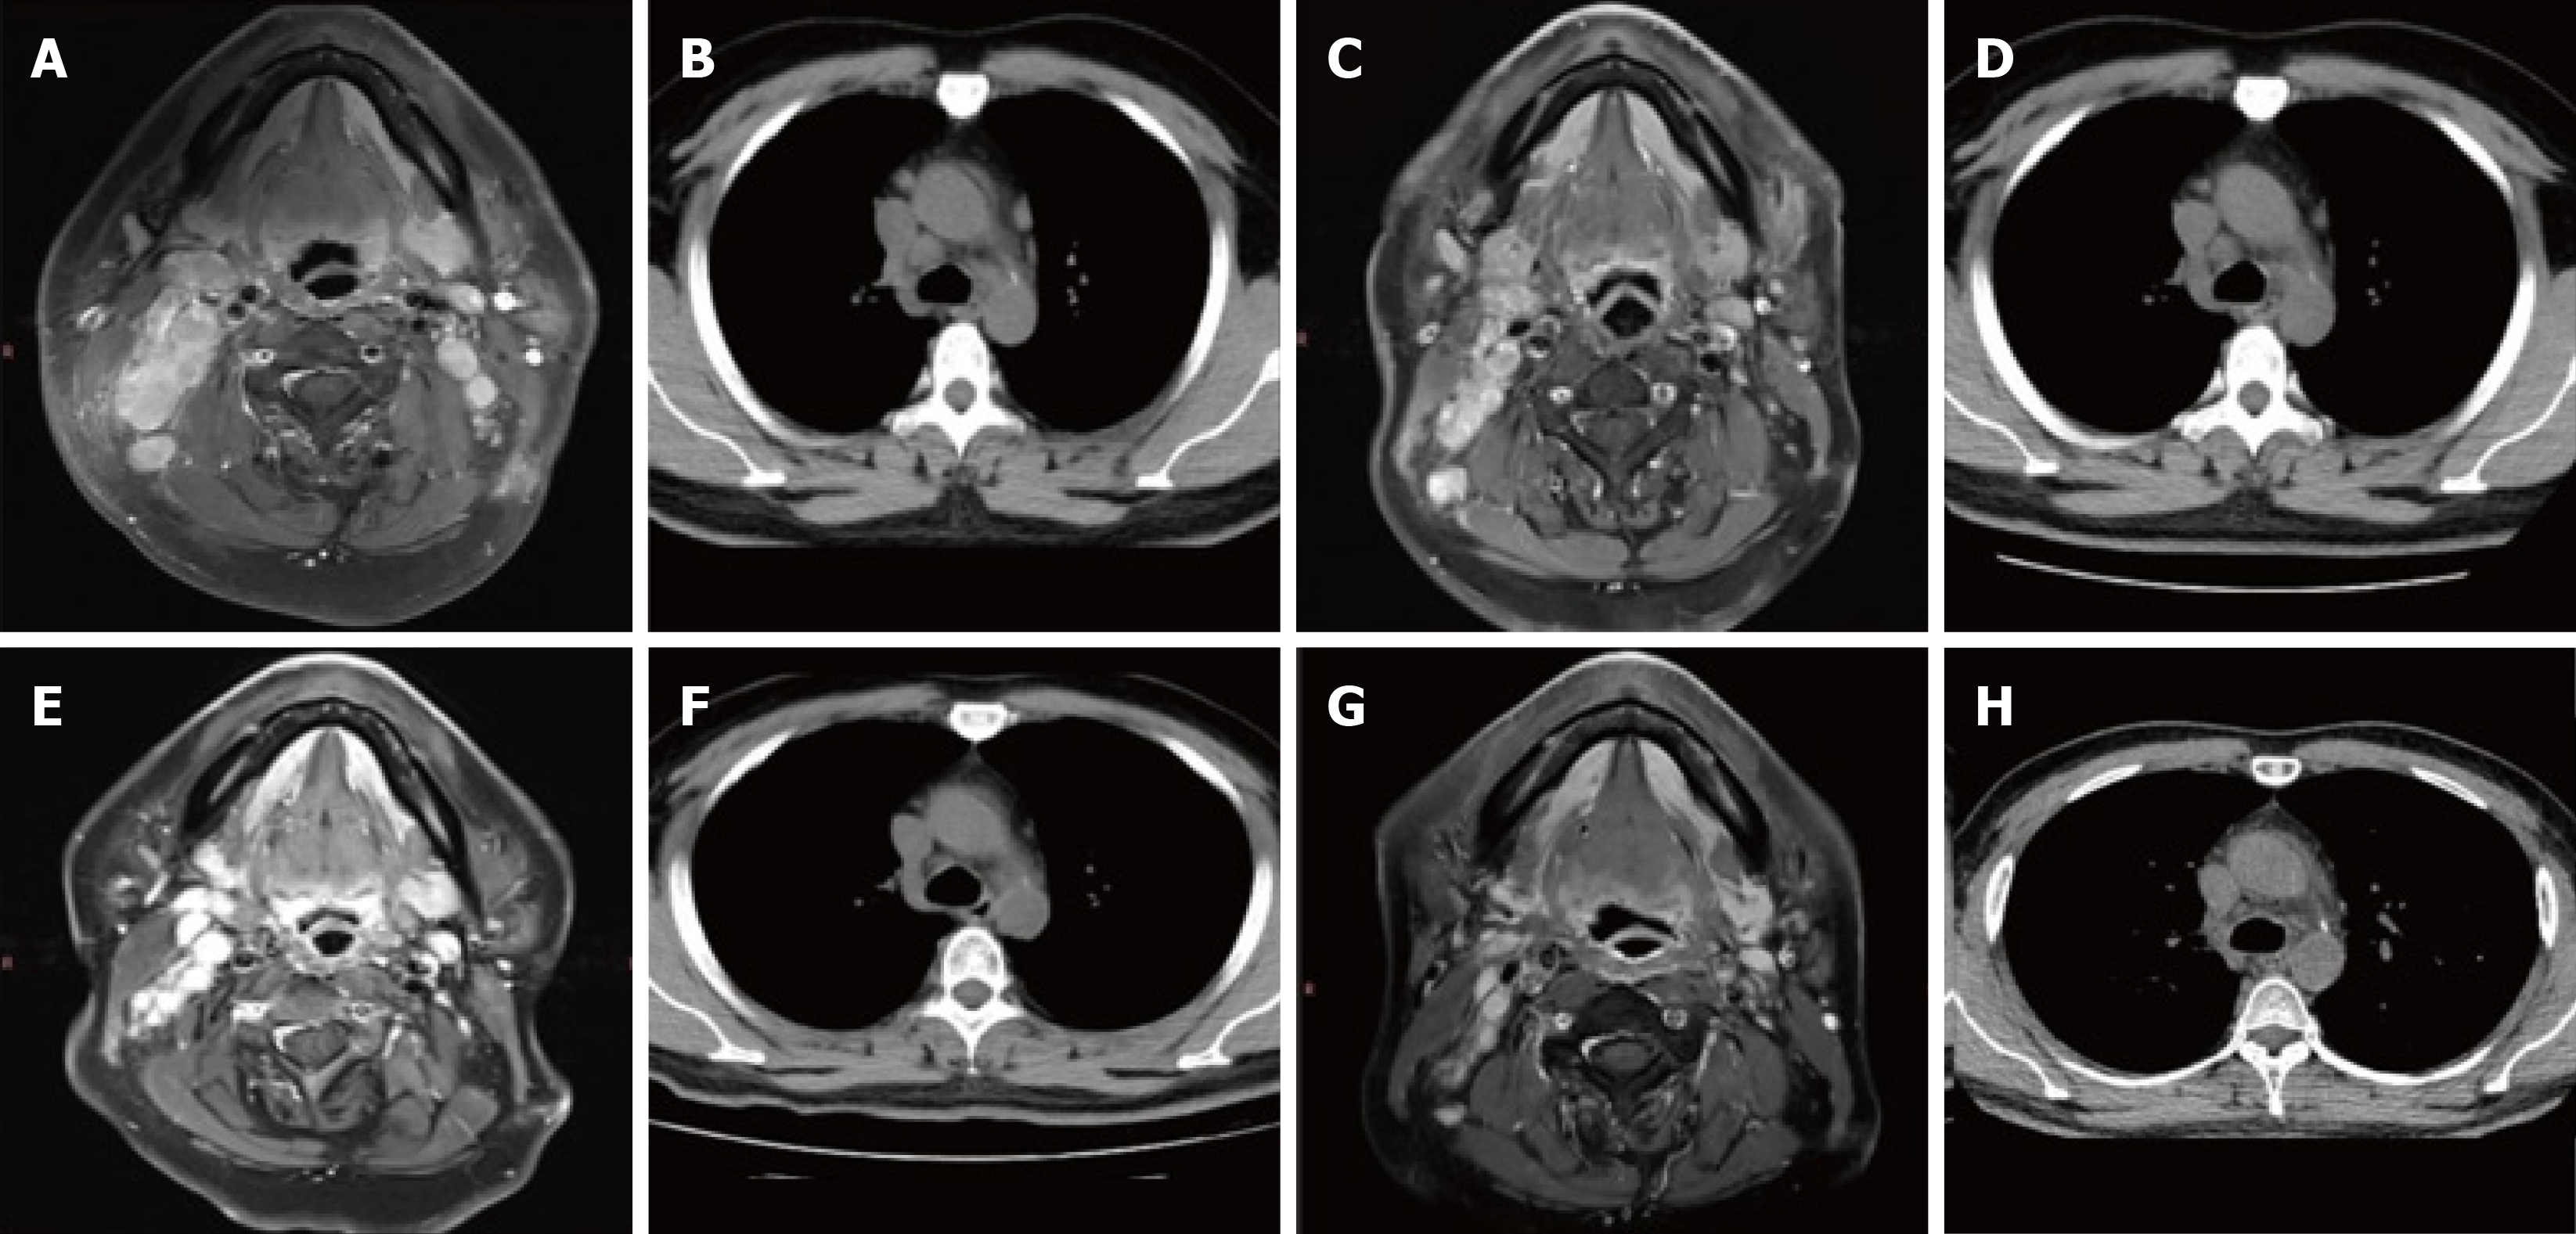

Figure 5 Nasopharynx magnetic resonance imaging (T1+C) and lung computed tomography findings of the nasopharynx.

A: Nasopharynx magnetic resonance imaging (MRI) (July 27, 2022) reveals multiple enlarged lymph nodes in both neck and retropharyngeal groups, with enhancement, partial necrosis, and fusion; B: Lung computed tomography (CT) (August 27, 2022) reveals multiple enlarged lymph nodes in the right neck, bilateral hilum, and mediastinum; C: Nasopharynx MRI (November 03, 2022) reveals that the range of lesions is slightly smaller than that in July; D: Lung CT (December 23, 2022) reveals that bilateral hilar and mediastinal lymph nodes are enlarged; E: Nasopharyngeal MRI (March 8, 2023) reveals that the range of lesions was significantly reduced compared to the October film; F: Lung CT (March 8, 2023) reveals that the range of lesions is significantly reduced compared to the November film; G: Nasopharyngeal MRI (July 5, 2023) reveals swelling and resolution of lymph nodes, diffuse swelling of submandibular soft tissue, slight thickening of the left side of the mucosa in the nasopharynx, and a more uniform signal; H: Lung CT (July 5, 2023) reveals lymph node enlargement subside.